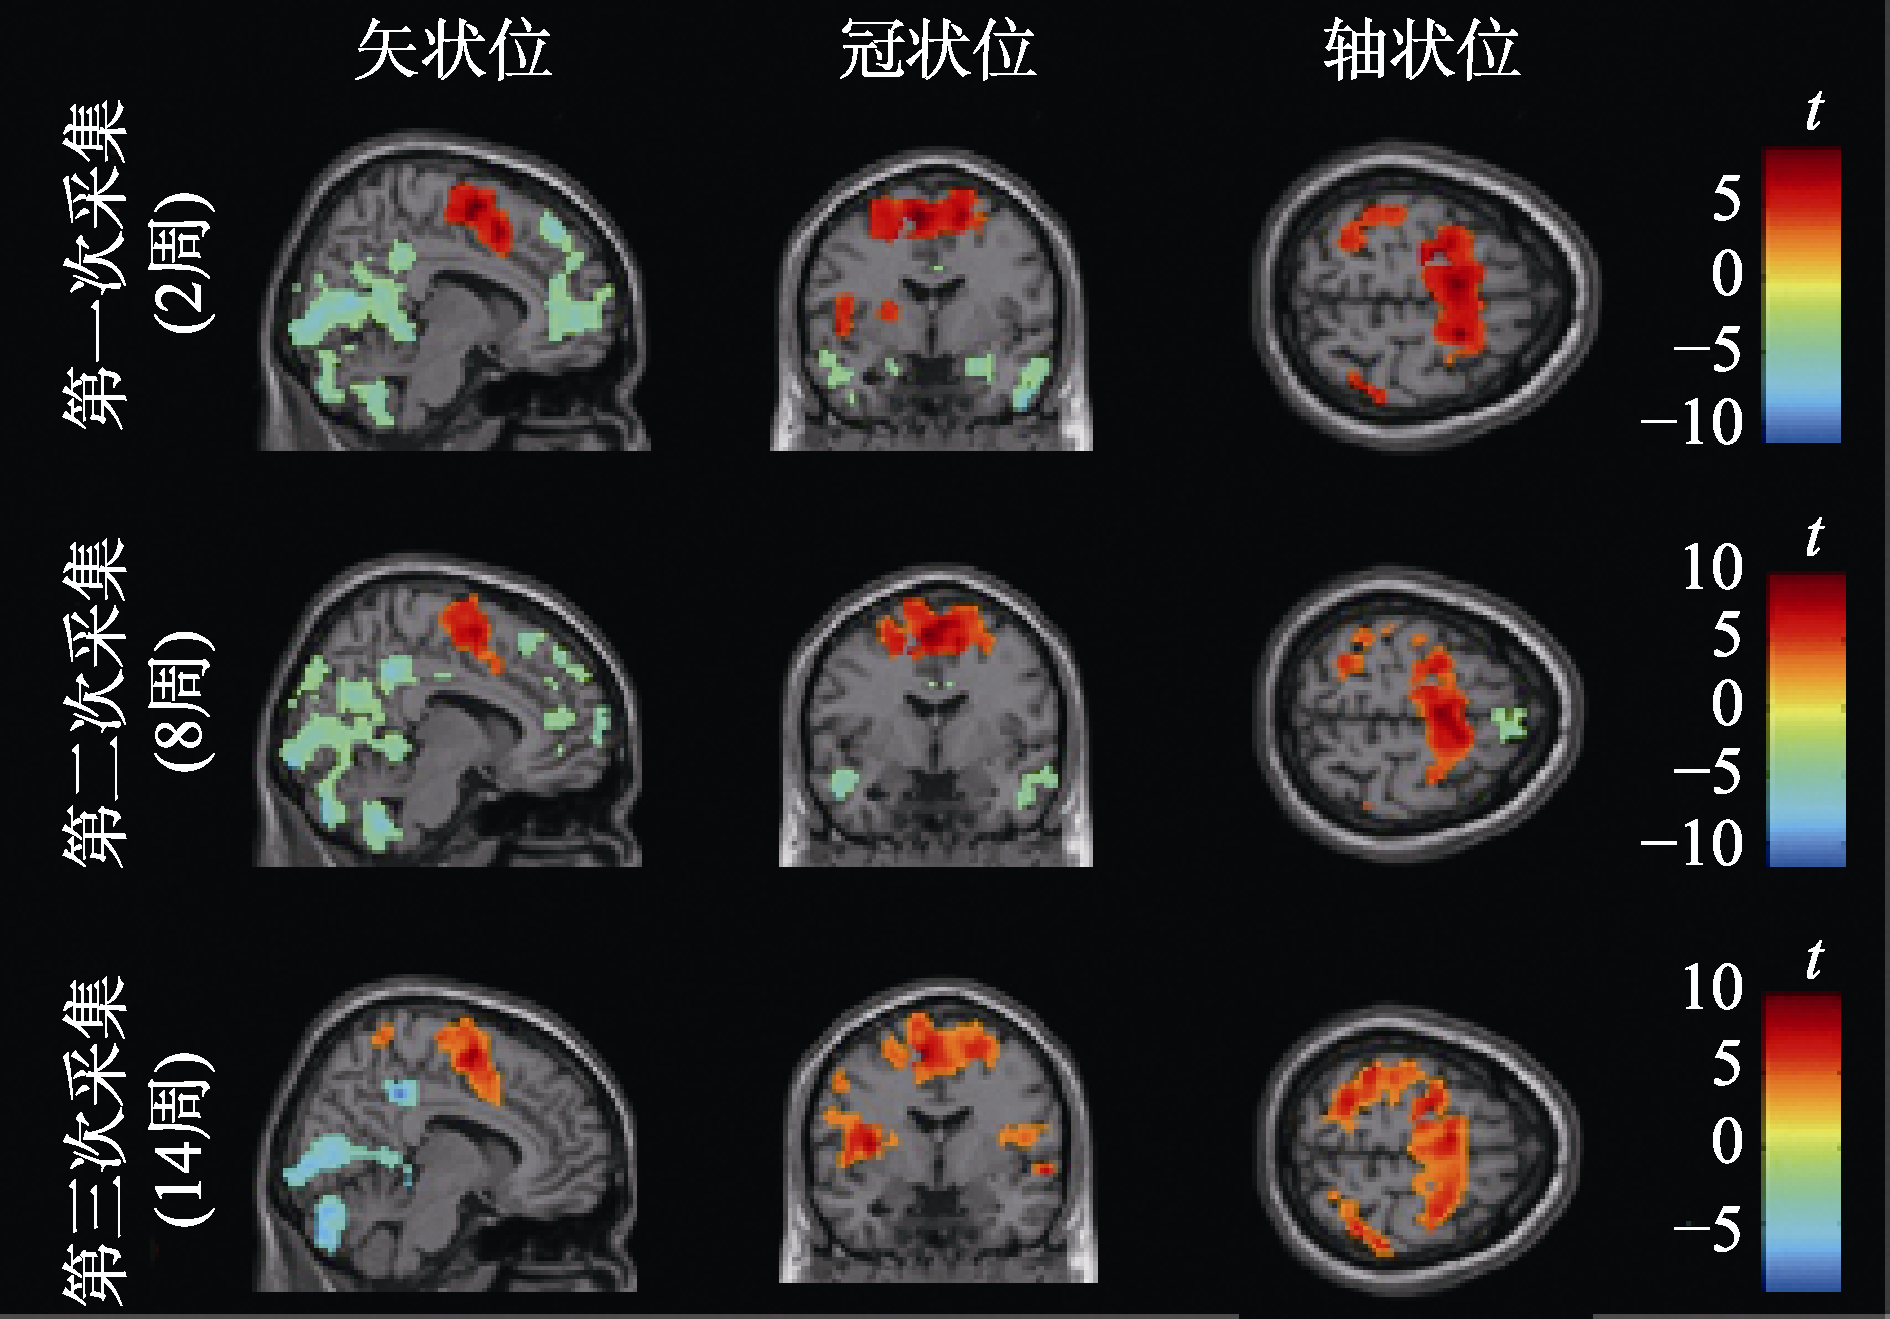

| 图4 不同时点运动表象激活的脑区 注:校正阈值为体素水平未校正, p < 0.001, 团块水平的FWE校正, p < 0.05; 第一次采集体素数量 > 147, 第二次采集体素数量 > 119, 第三次采集体素数量 > 55。 |